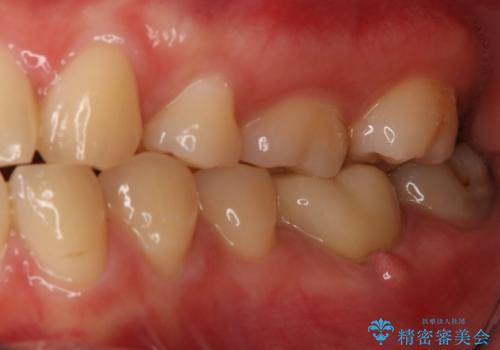

精密根管治療を行なったことで病巣は消失し、腫れや痛みは再発することなく経過は良好です。

被せ物はフルジルコニアクラウンを選択されました。